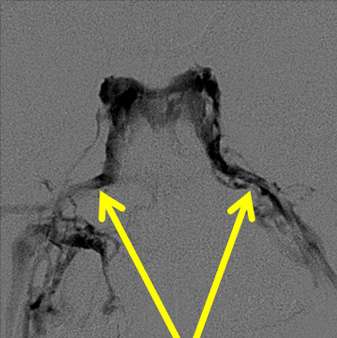

Picture of contrast injection of the inferior petrosal sinuses:

Typically under general anesthesia, we place small tubes (catheters) into the femoral veins (the main vein draining the legs) at the level of the groin. From there, under X-ray guidance, we navigate those catheters to the main veins which drain the Pituitary gland. These are the inferior petrosal sinuses (right and left). We then draw samples from those veins and the main vein of the abdomen and test those samples for ACTH. We also take timed samples after giving a dose of medication which would normally stimulate the production of ACTH to improve the sensitivity of the test.